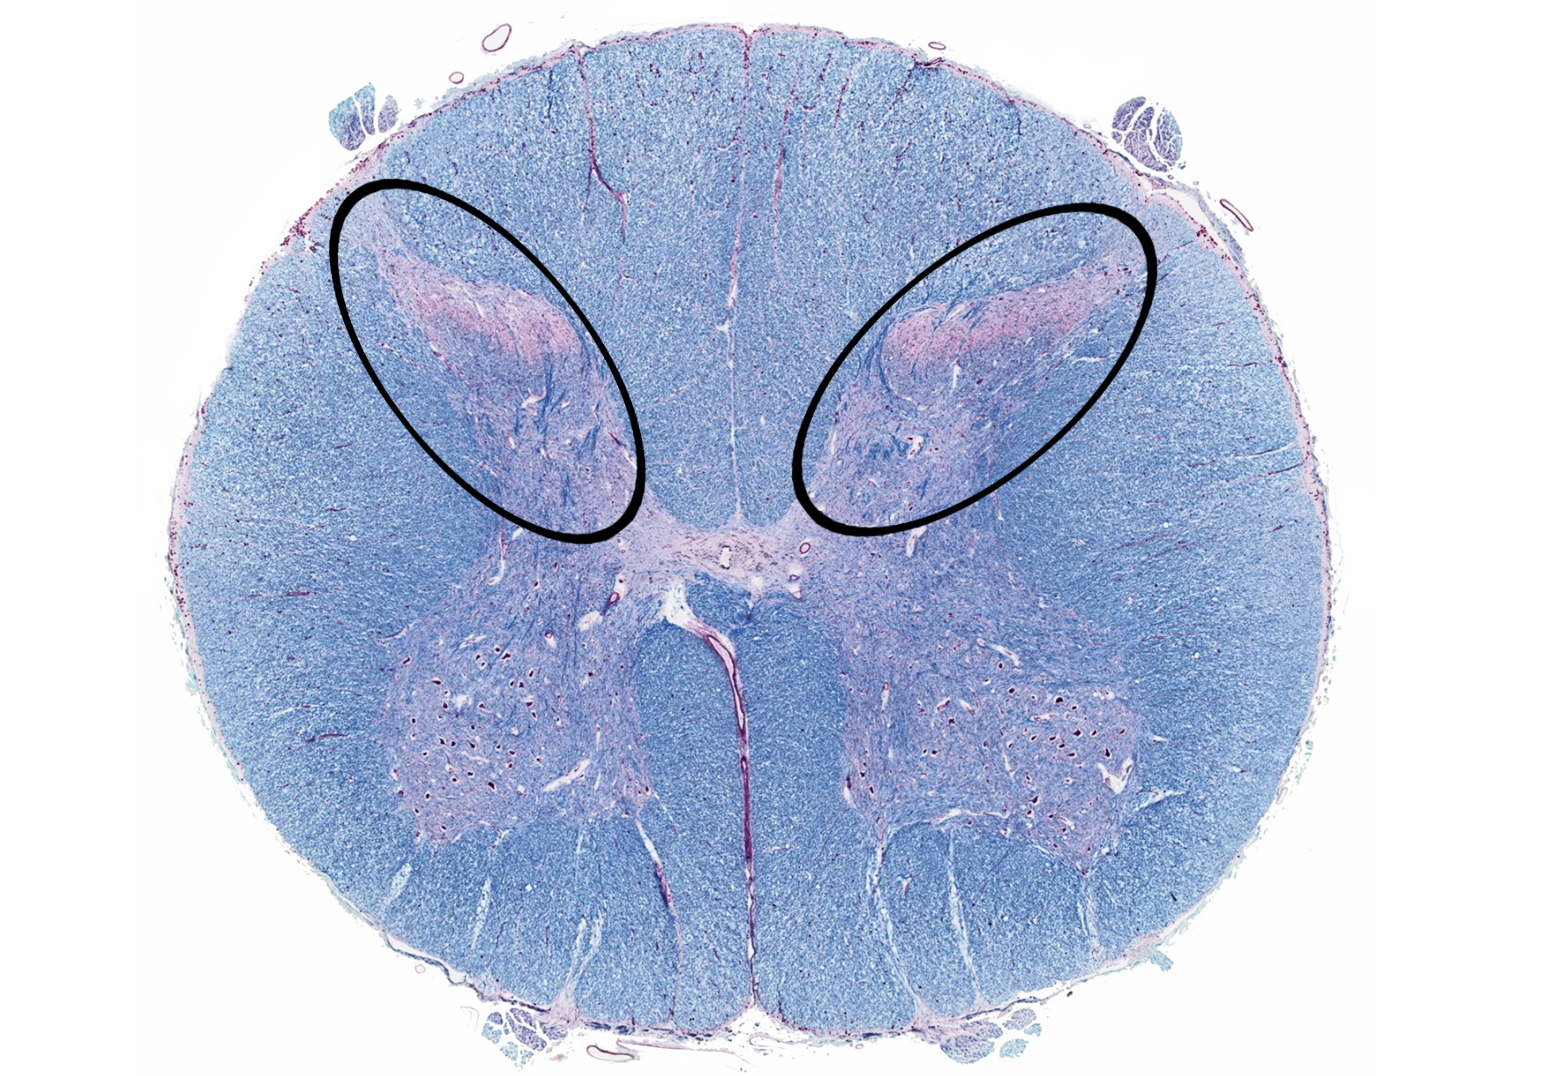

posterior horn

anterior horn